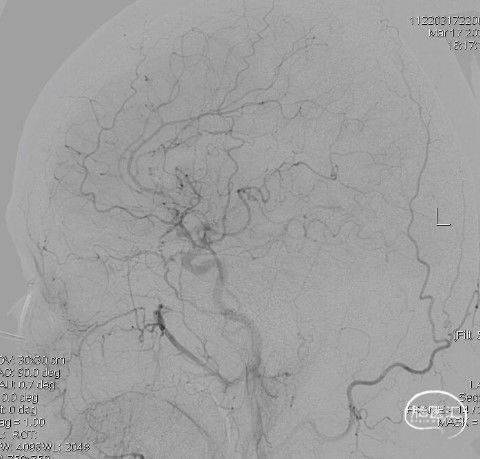

造影:右侧颈内动脉末端变细,大脑前及大脑中自起始部闭塞,脑底少量烟雾血管形成,汇聚使R-MCA少量分支显影。

右侧颈内动脉正位:

右侧颈内动脉侧位: